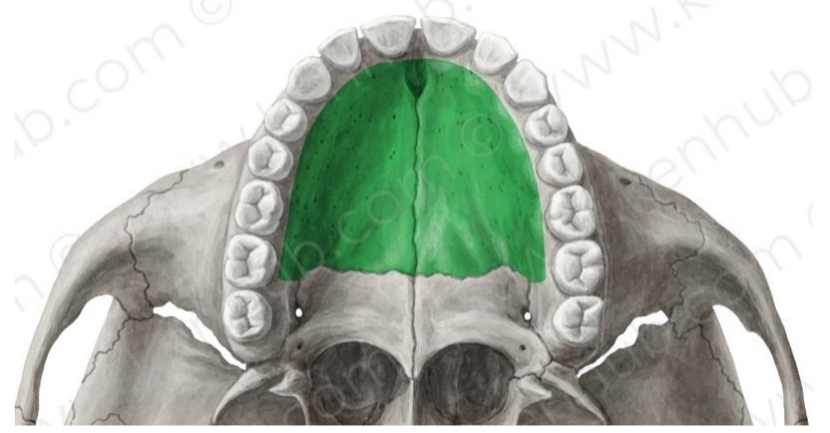

Hard palate

2 processes (R & L) that form roof of mouth or palate

Joints inner (lingual) portion of alveolar process

Palatine Process